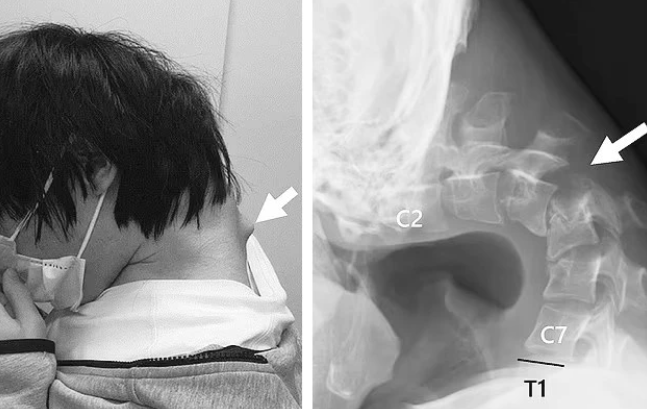

Recently, a 25-year-old man suffered from torticollis after a long period of using his phone to play games. His neck became so weak that he could not lift his head on his own. Imaging revealed that his neck was deformed with a noticeable bulge, caused by the vertebrae being abnormally stretched over a long period. It is known that the patient endured severe neck pain for six months before seeking hospital treatment. He also had difficulty swallowing, leading to reduced food intake and significant weight loss.

This case was published in JOS Case Reports with the consent of the patient and family.